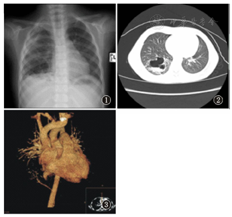

X线表现:右肺纹理模糊毛糙,右肺外带稍致密,右下肺可见多个大小不等囊状透亮影及条、线状及环形致密影(图1);胸部CT平扫:双肺纹理增多、毛糙,右下叶可见大片状影,其内可见大小不等囊状改变,可见气液平面(图2);胸部增强CT扫描+血管重建:腹主动脉上段分出一细小血管绕行后伸入右下肺病变(图3)。